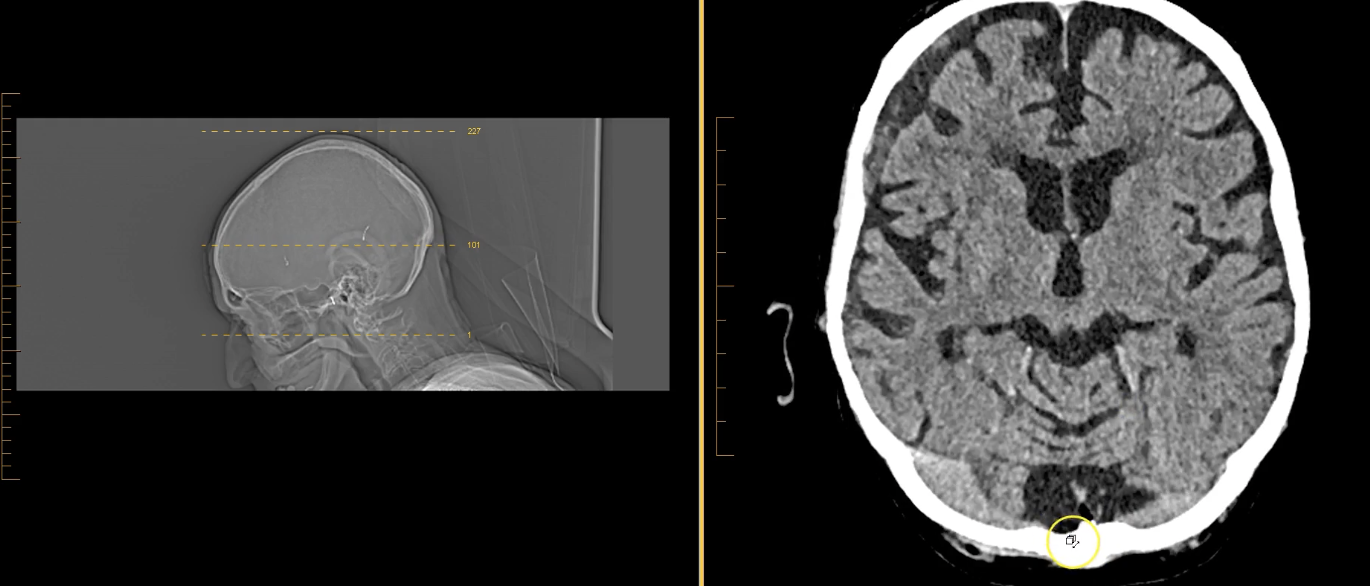

term image

thalamus